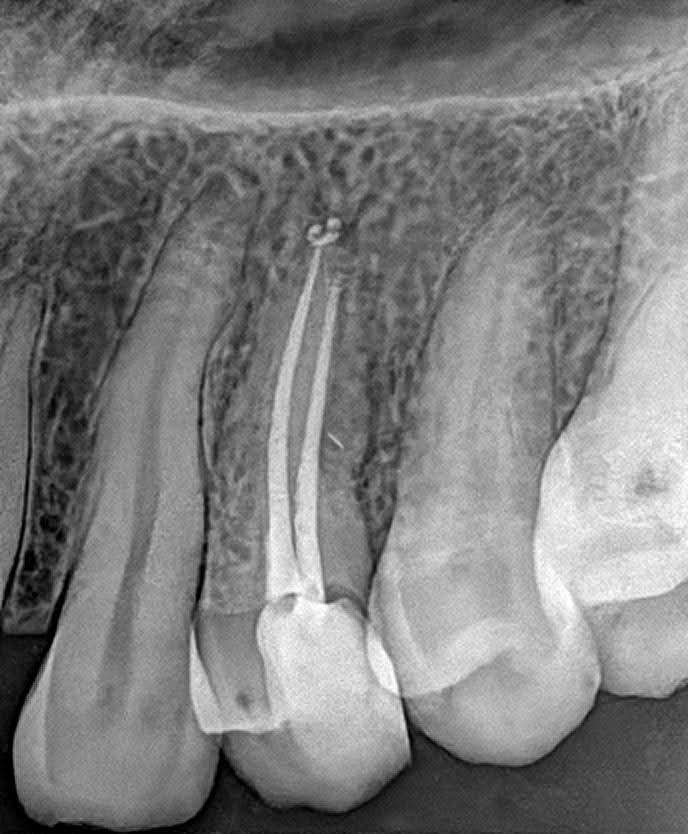

La endodoncia, comúnmente conocida como tratamiento de conducto, es un procedimiento dental que elimina el tejido pulpar afectado. Este tratamiento no solo alivia el dolor, sino que también previene la pérdida de la pieza dental, permitiendo que los pacientes mantengan su sonrisa natural.

Caso clínico realización de Tratamiento de Conducto: